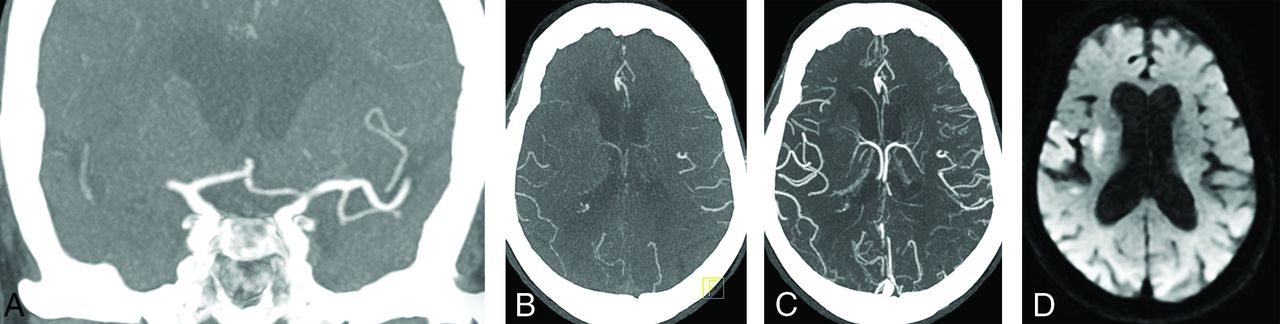

Coronal arterial phase mCTA MIP image demonstrates right M1 segment occlusion (A). Axial arterial phase mCTA MIP image (B) shows filling of at most 50% of distal branches. Axial delayed phase mCTA MIP image (C) shows filling of most distal branches. The patient underwent mechanical thrombectomy with restoration of TICI 2c flow. Follow-up diffusion-weighted MR image shows a small infarct core. If only sCTA had been used in this case (analogous to the arterial phase of the mCTA, B), the collateral status would have been classified as “poor to moderate distal collaterals” instead of “good collaterals.”

Right M1 segment occlusion. mCTA axial MIP images from the arterial phase (A), early venous phase (B), and late venous phase (C) show progressive collateral filling of distal MCA branches. The patient underwent endovascular recanalization with restoration of TICI 3 flow. Follow-up diffusion-weighted MR image shows a small infarct core.